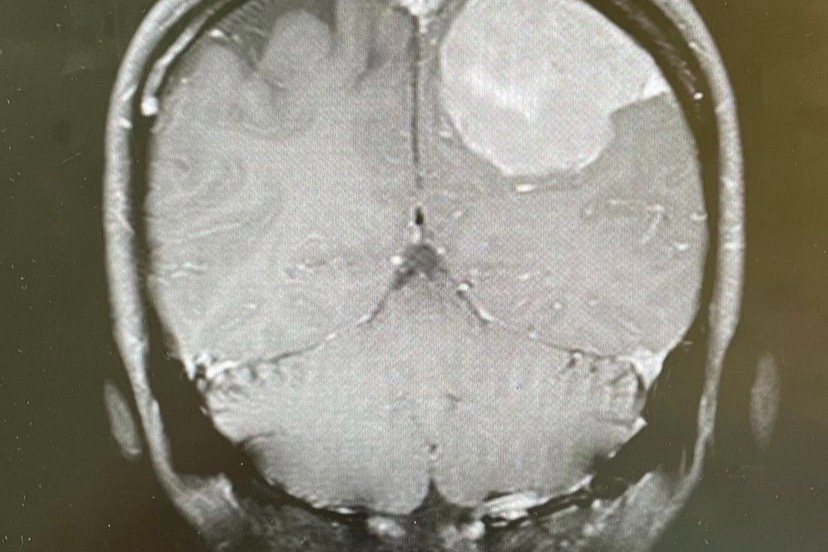

Kayo started feeling heart palpitations, vertigo and signs and confusion suddenly one evening. She rushed to the hospital where she was taken to urgent care. A scan revealed that she had a 6-inch tumor in her brain, which if not removed would take her life.

Surgeons acted quickly and were able to removethe tumor and Save Kayo’s Life !